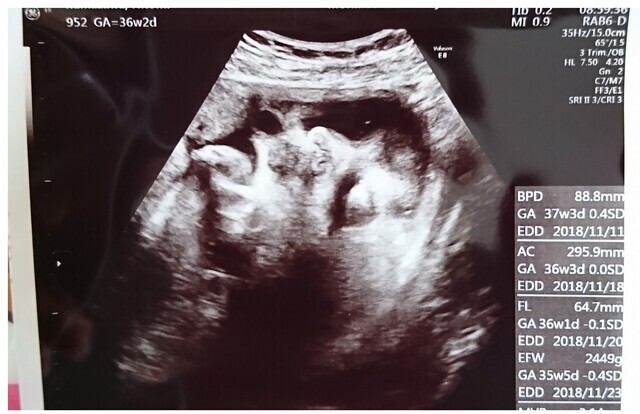

36週2日(36w2d・女の子)|サイ さん(35歳)

エコー写真撮影時のエピソード:

初めてエコーを見て、うちの子は本当に目が大きい。 ほっぺはかわいいすぎて早く会いたくて、生まれてきたら顔は本当にエコーようにかわいいです。

毎日、見ても幸せになります。 この子を生まれてきて良かった。 ありがとう、パパとママの娘。